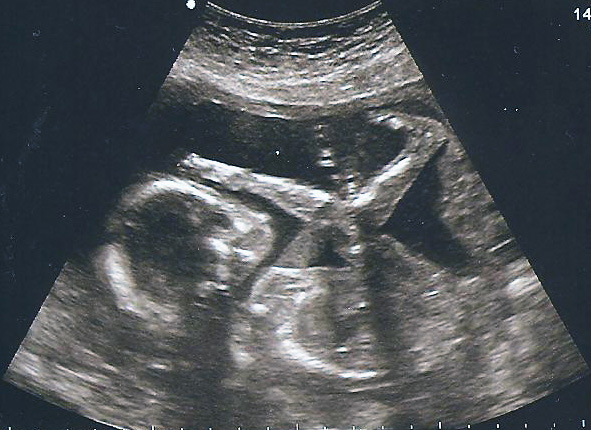

The latest statistics indicate that about 28% of American women under the age of 65 have had at least one abortion. I have met patients who have had as many as 8 abortions. It is a common procedure, and it used to be much more frequent back in the 1990s.